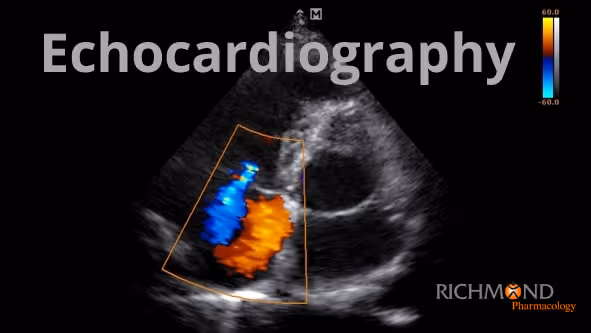

Richmond Pharmacology CEO, Dr Jorg Taubel, Franklin Gordon, Resuscitation Simulation & Clinical Skills Practitioner and Dr Simon Coates, Research Physician respectively, all began inhouse training for a BSE Level 1 Echocardiography this February.A Level 1 Echocardiography is designed to be accessible to echocardiography practitioners from a wide variety of backgrounds, and has, at its ultimate aim, the achievement and maintenance of high standards of clinical echocardiography to rule out life threatening and immediately reversible pathology in a time frame appropriate to the acute emergency patient.The course will run over a 2-year duration and qualify the individuals for a BSE Level 1 Qualification.